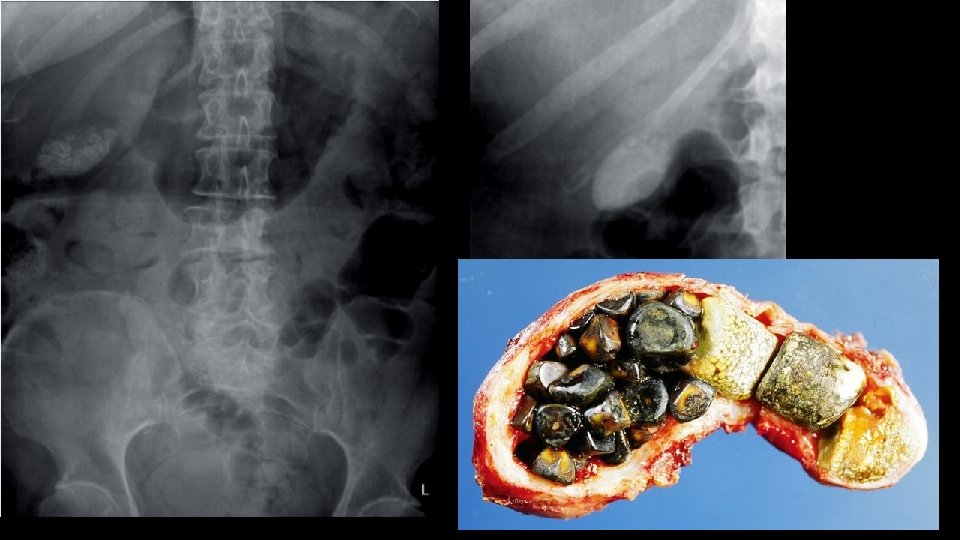

C for calcifications • Calculi – here, there and everywhere • Organ calcifications

Urolithiasis Calculi along urinary tract • Anywhere • Kidney • Ureter • Bladder

Chemical composition of calculi • Calcium containing Calcium Oxalate – metabolism derangement Struvite – UTI with urea splitting organisms • Devoid of calcium Cystine Uric acid Protease inhibitors